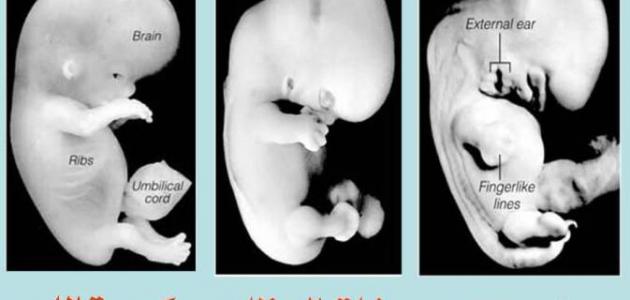

- المُضغَة: ذُكِرَت كلمَةِ مُضغَة فِي القرآن الكريم ثلاث مرّاتٍ وَهِيَ تَدل على قِطعَةٍ صَغيرَة مِنَ اللّحم بقدرِ ما يَمضَغَهُ الإنسان، وتبدأ هذِهِ المَرحَلة فِي الأسبوع الثالث بمرحلتين هُما:

- مضغة غير مخلّقة: تبدأ مِنَ الأسبوع الثالث حَتّى الرابع، ولا يكونُ في هذه المرحلة هُناكَ أي ظُهورٍ لأيِّ عُضو وجِهاز.

- مُضغَة مُخَلّقة: تبدأ هذِهِ المَرحَلة مِن بِدايةِ الأسبوع الرابع حَتّى الشهر الثالث، وهناك تَغيّراتٍ مُدهِشَة للجنين، وَتَنمُو الخلايا وتتمايز ليصبح عِبارة عَن إنسان قويم صغيرُ الحَجِم.والدليل على هذا الأمر قَولِ الله تعالى : (يَا أَيُّهَا النَّاسُ إِنْ كُنْتُمْ فِي رَيْبٍ مِنَ الْبَعْثِ فَإِنَّا خَلَقْنَاكُمْ مِنْ تُرَابٍ ثُمَّ مِنْ نُطْفَةٍ ثُمَّ مِنْ عَلَقَةٍ ثُمَّ مِنْ مُضْغَةٍ مُخَلَّقَةٍ وَغَيْرِ مُخَلَّقَةٍ لِنُبَيِّنَ لَكُمْ وَنُقِرُّ فِي الْأَرْحَامِ مَا نَشَاءُ إِلَى أَجَلٍ مُسَمًّى ثُمَّ نُخْرِجُكُمْ طِفْلًا ثُمَّ لِتَبْلُغُوا أَشُدَّكُمْ وَمِنْكُمْ مَنْ يُتَوَفَّى وَمِنْكُمْ مَنْ يُرَدُّ إِلَى أَرْذَلِ الْعُمُرِ لِكَيْلَا يَعْلَمَ مِنْ بَعْدِ عِلْمٍ شَيْئًا وَتَرَى الْأَرْضَ هَامِدَةً فَإِذَا أَنْزَلْنَا عَلَيْهَا الْمَاءَ اهْتَزَّتْ وَرَبَتْ وَأَنْبَتَتْ مِنْ كُلِّ زَوْجٍ بَهِيجٍ) سورة الحج:5

- العظام: قال الله تعالى :(فَخَلَقْنَا الْمُضْغَةَ عِظَامًا) سورةِ المؤمنين:14، فِي هذا الطور تتَحَوّل قِطعَةِ المُضغَة وَهِيَ عِبارَة عَن قِطعَةِ لَحِم إلى هيكَل عَظمِي فِي الأسبوع السابعِ تَحديداً ليكُونَ على شَكلِ صُورَةٍ آدَميّة.

- كساءُ العظام باللحمِ والعضلات: قال الله تعالى: (فَخَلَقْنَا الْمُضْغَةَ عِظَامًا فَكَسَوْنَا الْعِظَامَ لَحْمًا) سورةِ المؤمنين:14؛ فهذِهِ الآية تَدُلُّ على أنّ العظام تَتَكَوّن فِي البداية وَمِن ثُمّ يَكسُوها الله تعالى بالعَضلاتِ والّلحِم، وَيبقَى هذا الطور إلى نِهايَةِ الشهر الثاني (الأسبوع الثامن)، وَيبدأ بعدَها تَكوّن الجنين ونشأتهِ، وينتَهِي طَورِ الأجنّة بِحَسَبِ ما يَصِفَهُ العُلماء.

- الخلق الآخر (نشأةِ الجنين): فِي بِدايَةِ الأسبوع التاسع تُصبِحُ الأعضاء جاهِزَةً بأن تَقُومَ بِوظائِفِها، وفي هذِهِ المَرحَلَة يَنفُخُ الله تعالى الروح على الجنين بَعدَ مرورِ أربعةِ أشهر من الحمل.